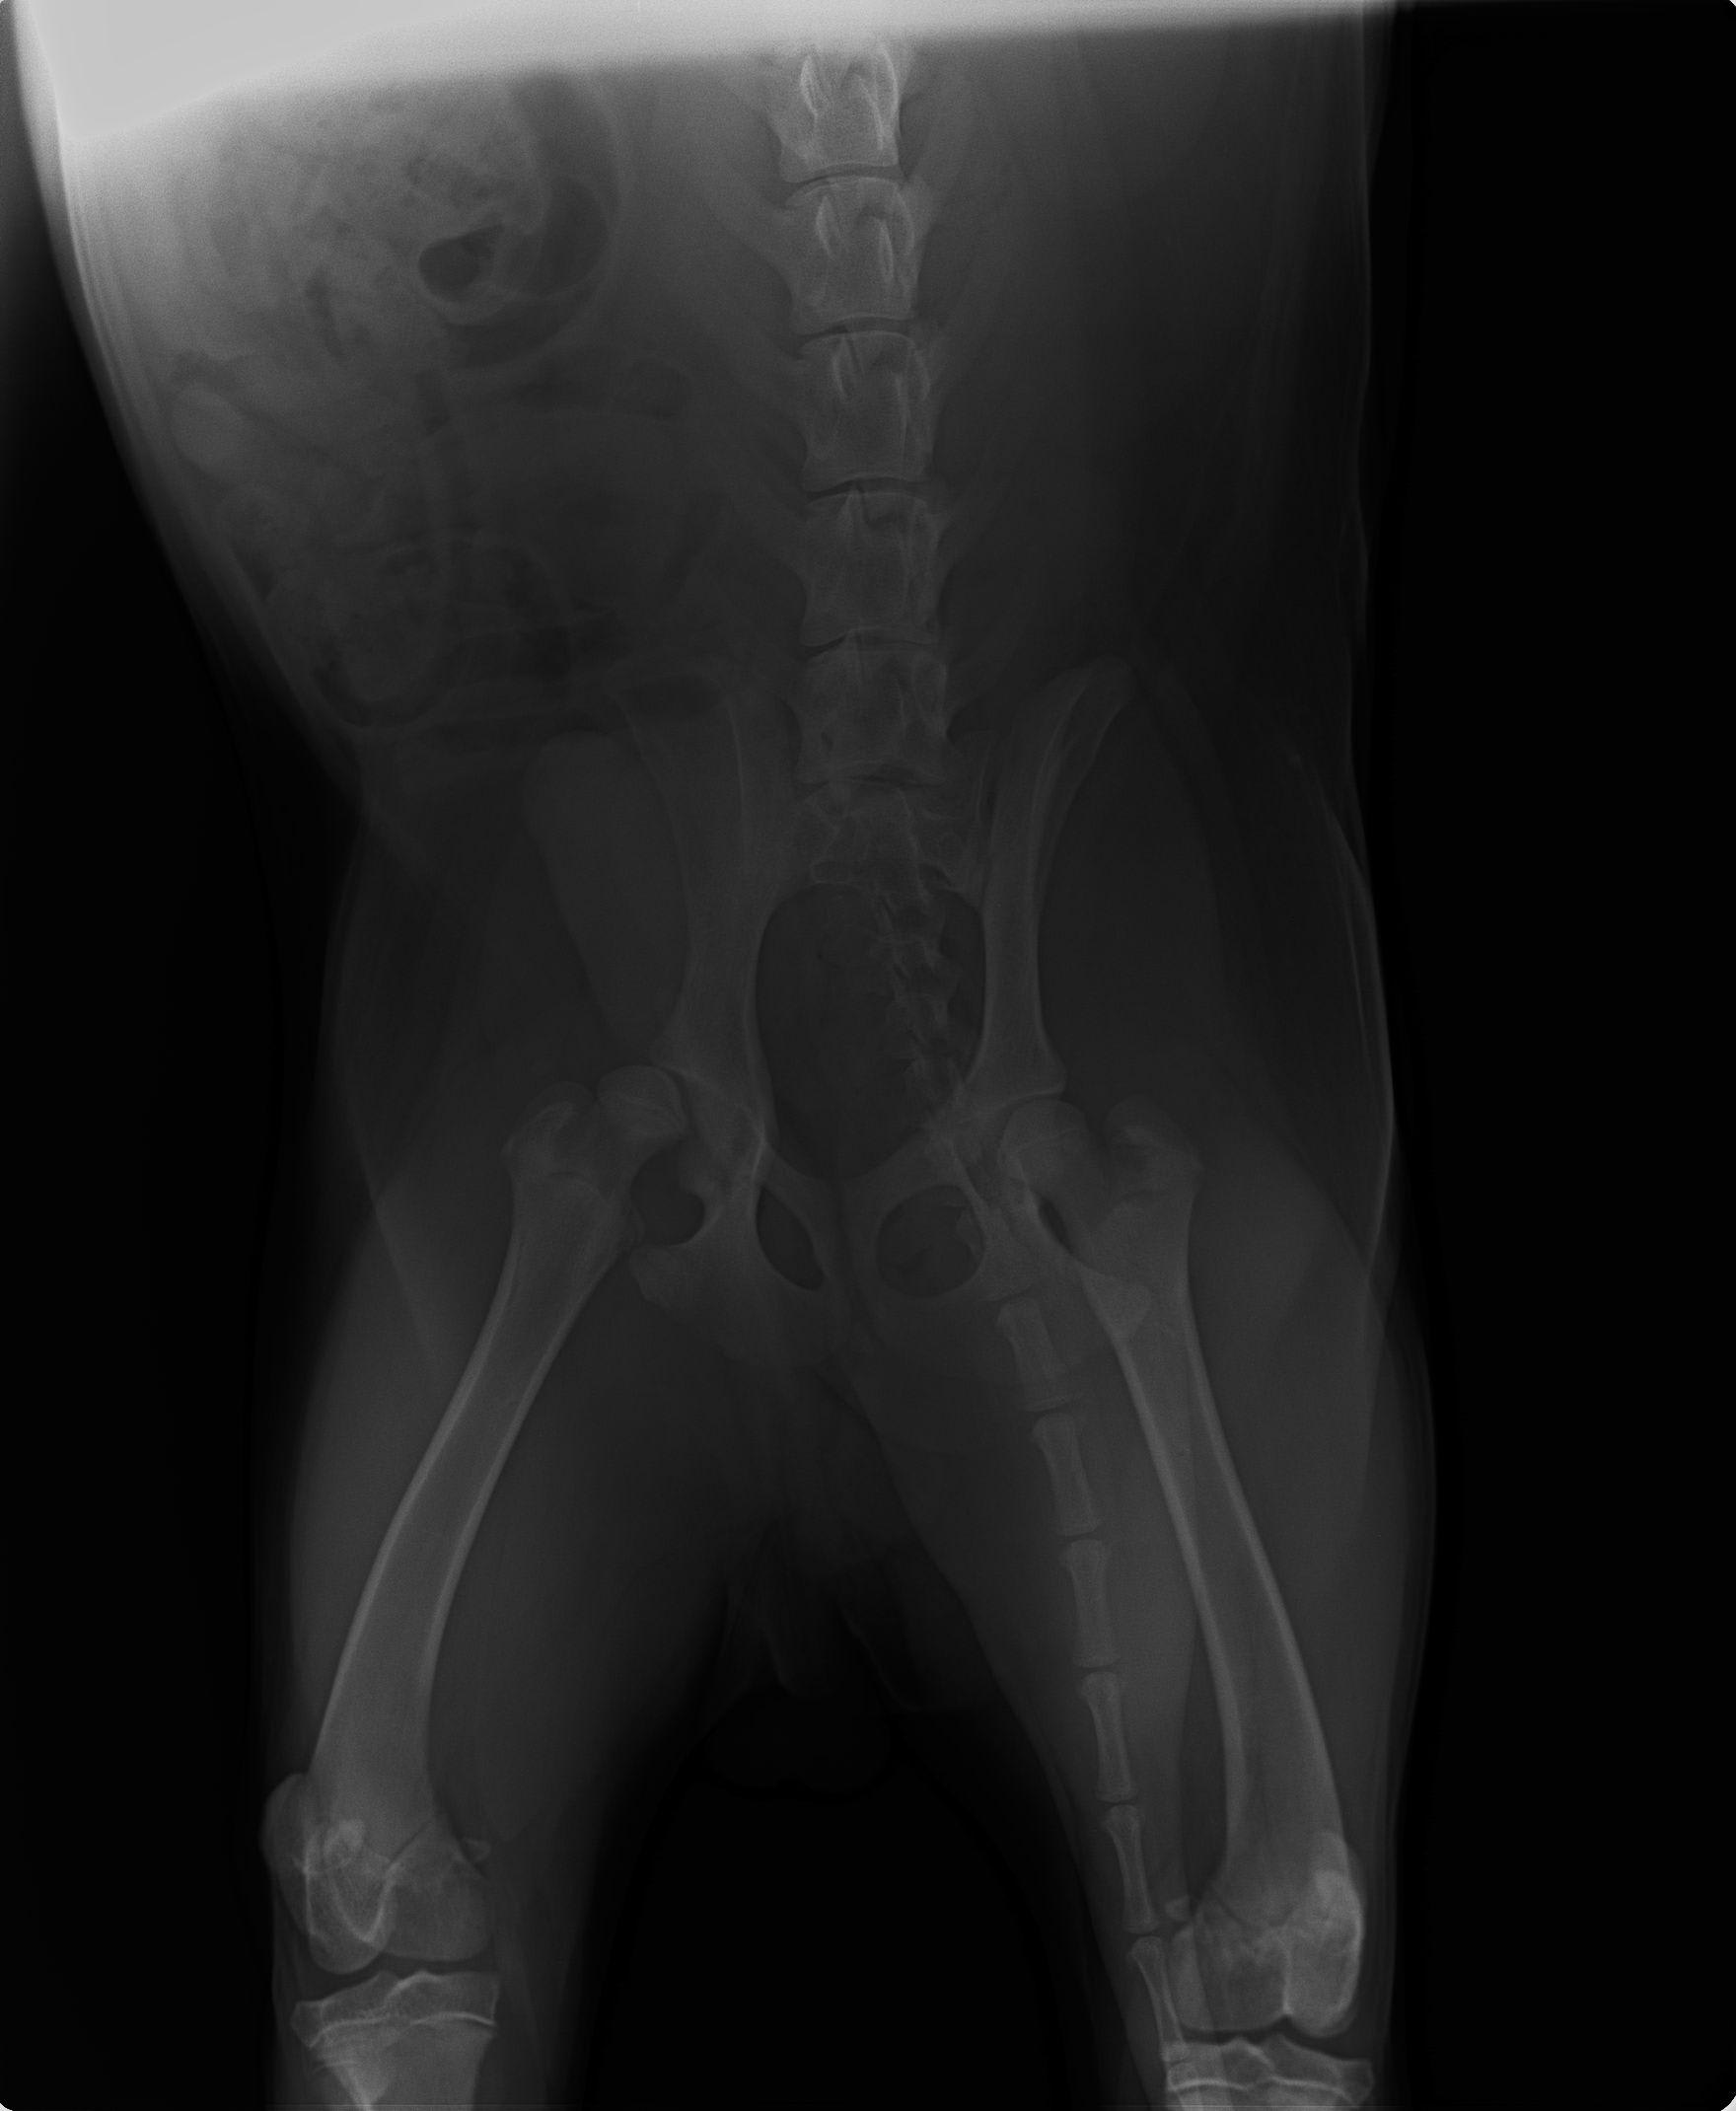

My dog has hip dysplasia in both of his back legs. He is labrador 33kg /75 lb weight. I consulted nearly all my vets in my state but all said he has to go through surgery which will cause lameness for his entire life and as its in both legs it quite risky too. They say that the surgery is about pain but he does not feel any pain he runs around the house all day. I don't want him to remain lame his entire life as he only 10 months old. All vets say surgery is only option. So i am confused...

Hello, sorry to hear about Shiro. He does indeed have hip dysplasia as is evident in his x-rays. This diseases does indeed require surgical correction, but only if Shiro seems to be in discomfort. Hip Dysplasia results in secondary osteoarthritis which in the long term can impact your pets ability to walk and overall comfort. There are two different procedures with regards to surgery, an FHNO were we remove the femoral head and neck or a total hip replacement were we replace the ball and joint with metal implants as they do in humans. Ultimately, the best contributor to decreasing osteoarthritis in dogs is by maintaining an overall low weight and lean body condition score. Obese pets with hip dysplasia tend to do worse. Now, with regards to surgery, it does not need to occur now, typically with either surgery, we want pets to be fully developed so that their bones are fully grown and they have developed all of the musculature. I would recommend asking your veterinarian to refer you to an orthopedic surgeon who may be able to better assist you with Shiro's hips dysplasia. Hope this helps and best of luck.